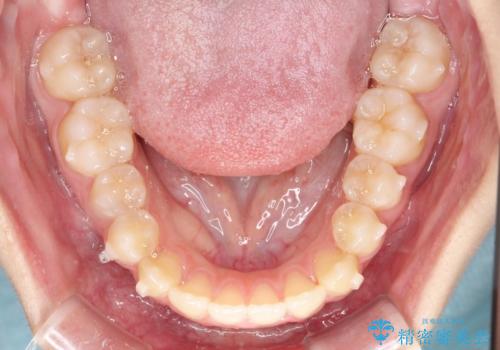

- 右上の小臼歯が大きくねじれており、噛み合わせや見た目に影響を与えている状態でした。診察の結果、インビザライン単独では十分な回転が得られにくいと判断。そのため、基本的な歯列の移動はインビザラインで行いながら、部分的にワイヤー矯正を併用するコンビネーション治療を計画しました。

まず、インビザラインで歯列全体を整えながら、スペースを確保しました。その後、部分ワイヤーを装着し、右上小臼歯の捻転を効率よく改善。ワイヤーの力を活用することで、より確実に歯の向きを整えることができました。治療後は、「しっかり噛めるようになり、見た目も自然になった」と患者様にもご満足いただきました。